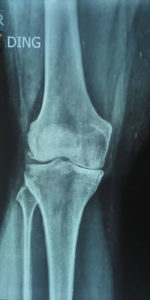

Pre Operation X-Ray for Partial Knee Replacement Surgery